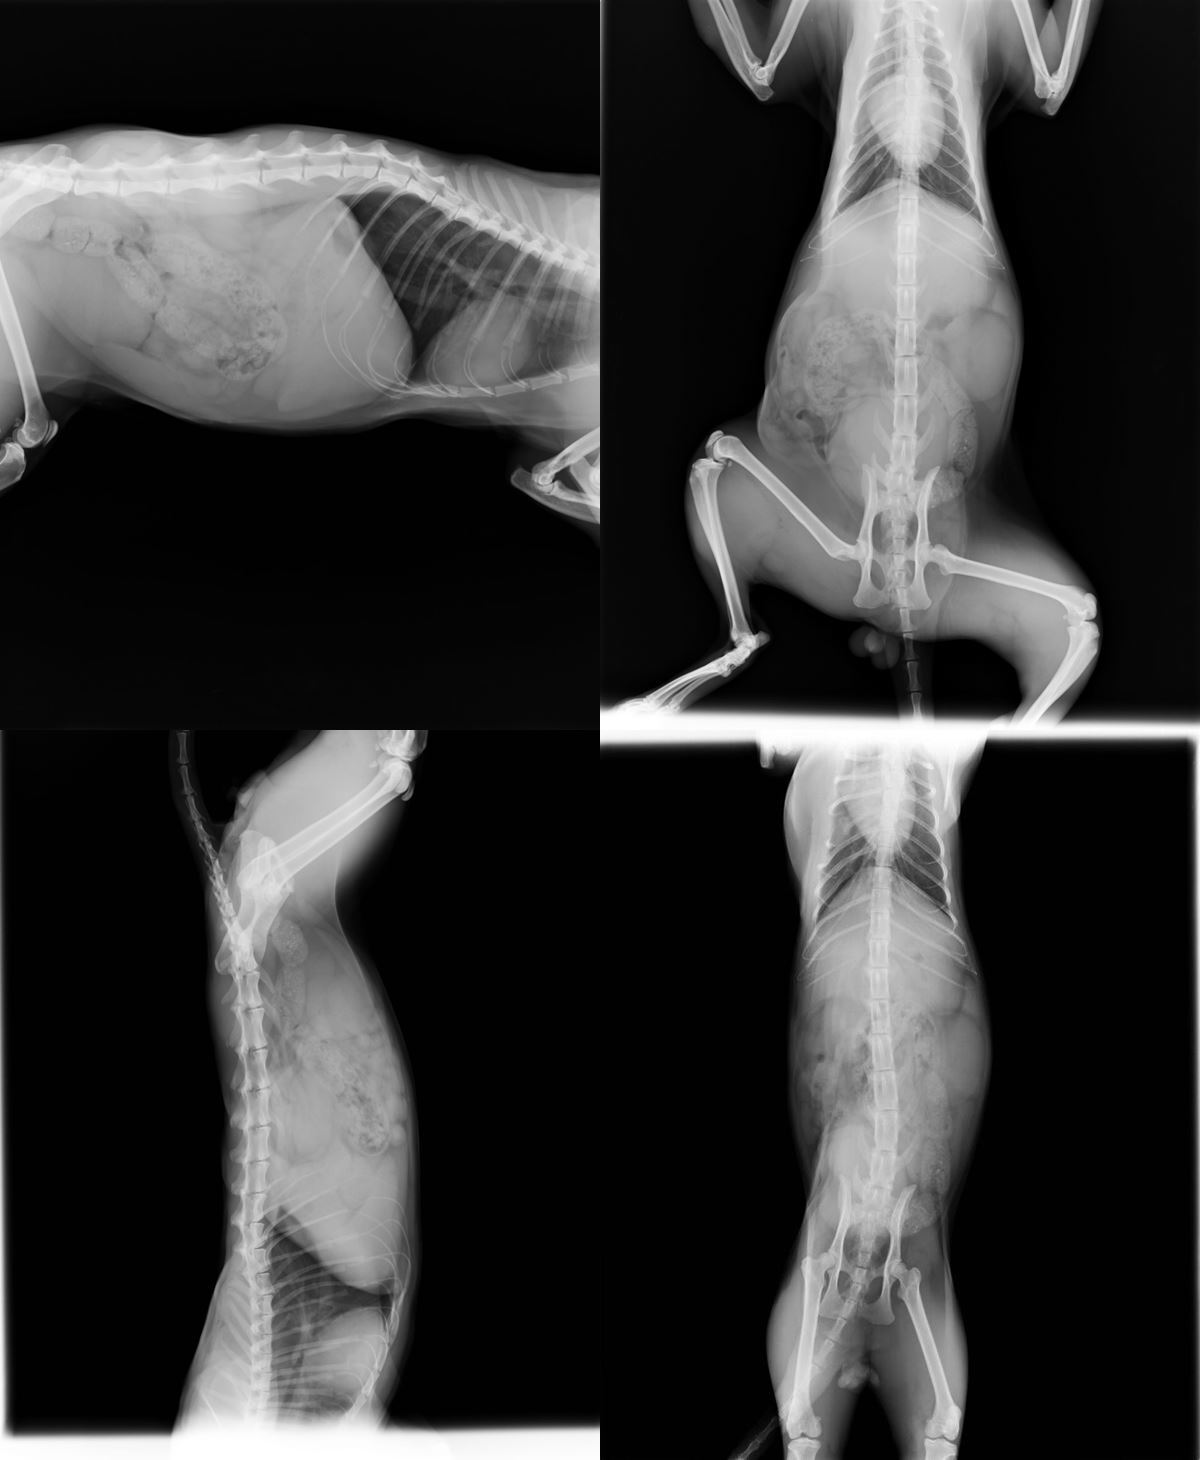

主題: 創傷造成的疝氣大橘貓 申請者姓名: 許桂菱 花色: 申請日期: 2016-02-11 14:34:31 申請者部落格: 申請者臉書網址: 所在縣市/合作醫院: 台中市/春天動物醫院 治療費用: 8000元 需求人數: 19人 已結案 (2024-06-01 13:40:54) 報名人員: cherry.shu x10(已付款)、圓滾滾的狐狸(已付款)、何智喬(已付款)、Wang Yungting(已付款)、Akiko Tsai(已付款)、Pei Hong Lin(已付款)、Vivien(已付款)、Vicky(已付款)、Sharon Wang(已付款)、Ling(已付款)、 候補人員: 動物病情說明: 2015年10月底在服裝店前偶遇,當下有給予餵食,之後常刻意經過,餵食3~4次才發現右側腹呼吸時會起伏,本以為是腫瘤,也想進行誘捕就醫!後來不知是天氣不穩定或是時間問題,就沒再遇過此貓,然而這幾天連續有貓友提及寵物用品店前有隻受傷的橘貓,前往查看才發現竟然是同一隻橘貓!2/2進行誘捕送往台中春天動物醫院!

醫生判定是外力造成的腹腔破洞(疝氣),需進行縫合手術,評估橘貓狀況可順便結育!預計住院三天即可!

2/2 手術發現兩個破洞,右邊的腎擠出來,另外也同步處理結育,進行三合一血檢,貓愛滋及貓白血皆陽性